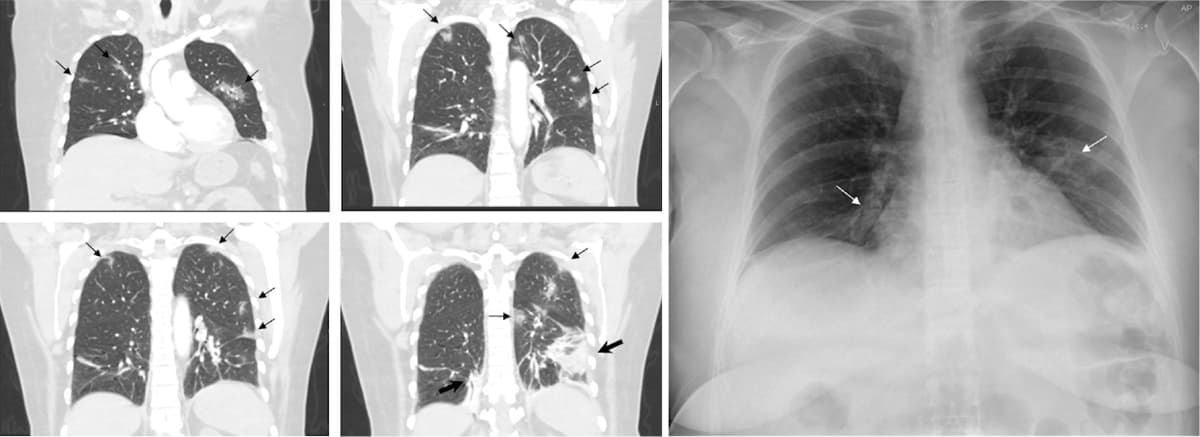

En 54-årig kvinde blev indlagt med en uges varende hovedpine, feber, tør hoste og tiltagende dyspnø. Hun havde på sit arbejde været eksponeret for severe acute respiratory syndrome coronavirus 2 (SARS-CoV-2), og flere blandt det øvrige plejepersonale var testet positive. Ved indlæggelsen havde hun en saturation på 93% på 2l ilt, en respirationsfrekvens på 21/min, en puls på 90 slag/min og C-reaktivt protein-niveaupå 38 mg/l. Et røntgenbillede af thorax viste kun diskrete infiltrative strøg (hvide pile). Patienten blev testet positiv for SARS-CoV-2. På grund af forhøjet D-dimer (1,46 mg/l (FEU)) blev der lavet en CT af thorax. Hermed afkræftedes mistanken om lungeemboli, men i stedet sås der bilaterale, perifere, multilobære matglasinfiltrater (vist med sorte pile) med konsolidering basalt (vist med fede sorte pile). De billeddiagnostiske fund var karakteristiske for coronavirus disease 2019 (COVID-19) [1].